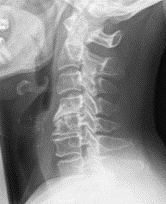

Im Bereich der Halswirbelsäule (HWS) ist es oftmals notwendig, die komplette Bandscheibe zu entfernen. Diese kann dann durch eine Bandscheibenprothese, die eine weitere vollständige Beweglichkeit der HWS ermöglicht, ersetzt werden. Diese Operation wird von vorn (ventral) durchgeführt.